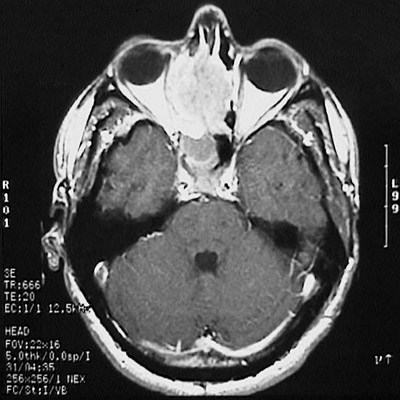

The MRI scan of the head in axial view reveals a mass lesion. This is an olfactory neuroblastoma filling and expanding the nasal cavity and adjacent sinuses on the right. This same mass is seen in coronal view below.